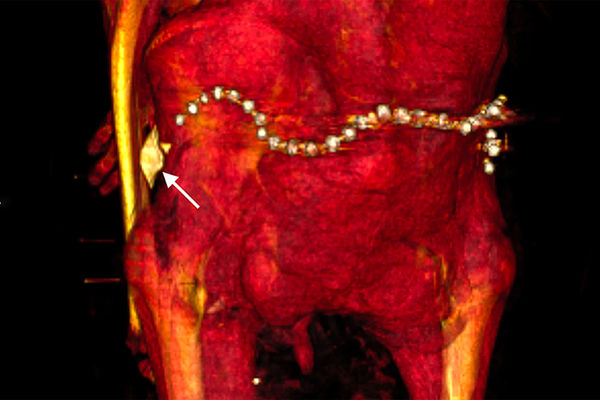

В бинтах исследователи также обнаружили около 30 украшений, в частности пояс из металлических (вероятно, золотых) бусин в задней части тазовой области, и фаянсовый амулет в форме раковины улитки у левого бедра.